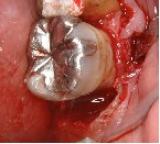

歯槽膿漏 | ||

| 歯槽膿漏によって失われた骨が再生しています。 | ![]() |

【術前】 |

【術後】 |